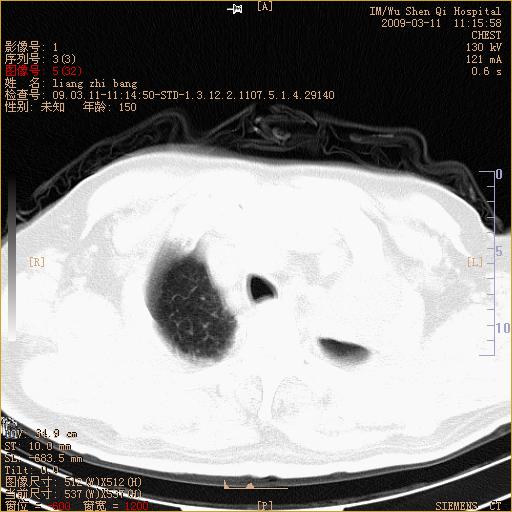

标题: CT18604:男,60岁,咳嗽一月余 [打印本页]

标题: CT18604:男,60岁,咳嗽一月余

1)考虑左肺上叶中央型肺癌并左肺上叶肺不张;建议必要时行纤支镜检查进一步明确诊断。2)左侧胸腔积液。

肺门肿块、支气管开口闭塞伴肺不张及胸水!典型的中心型肺癌变现!

1、左肺上叶中央型肺癌并上叶阻塞性肺不张。

2、左侧胸腔少量积液,右侧胸膜轻度增厚。